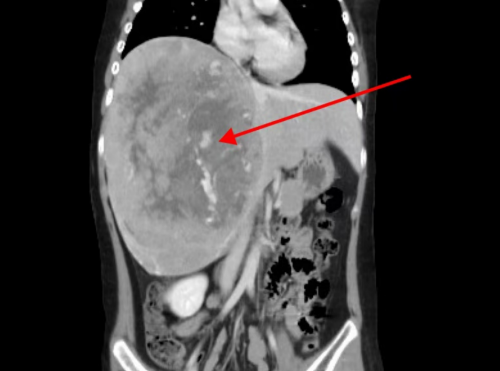

据该院急诊外科接诊医生王亮介绍,孩子入院时检查发现腹肌紧张,右上腹压痛,胸腹部增强CT提示:肝右叶肿块,考虑:肝母细胞瘤?合并肿瘤内出血。

CT检查显示肝右叶巨大肿块

手术中发现患儿右肝巨大占位性病变,约20cm*10cm*6cm大小,予以完全剥离,手术顺利,病理结果证实为“肝母细胞瘤”。术后转急诊重症监护室继续治疗。经过急诊科副主任、主任医师丁宁带领医护团队给予精心照护,患儿病情好转稳定,现已转出重症监护室,在急诊综合病房继续治疗。